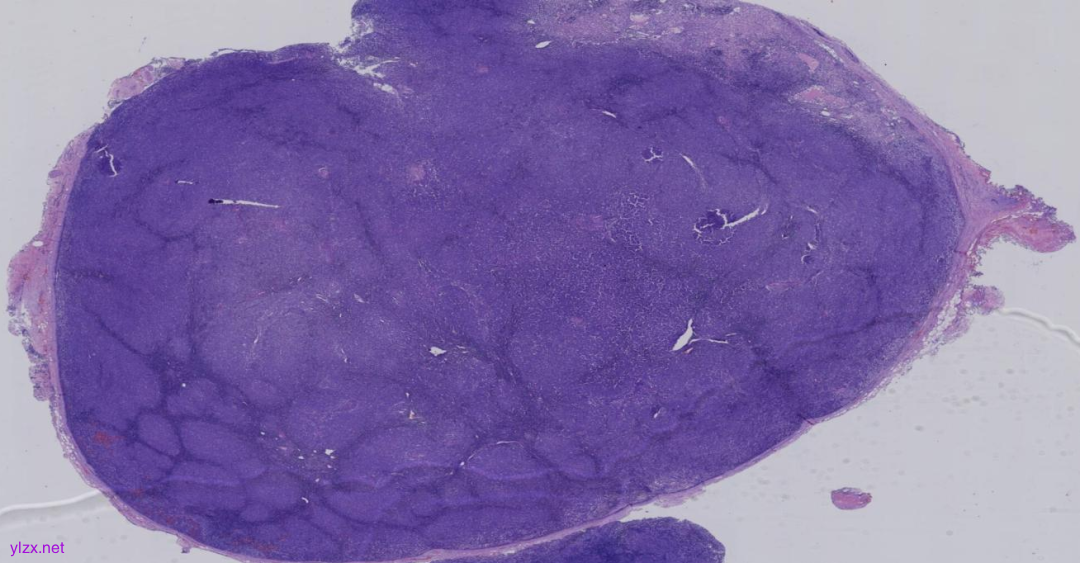

图1:低倍镜下淋巴结内见大小不等的结节状结构,是一个以结节性生长方式为主的淋巴组织增生性病变,局部淋巴结被膜增厚。